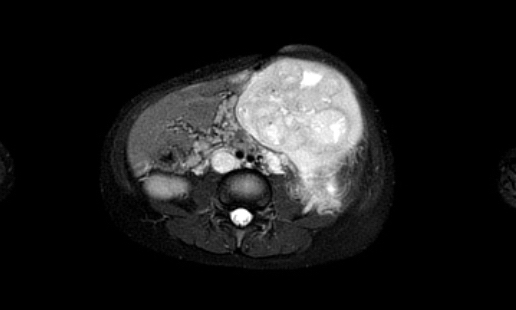

Hình ảnh MRI của một bé gái chín tháng tuổi có khối u ở bụng trái. MRI cho thấy khối u tuyến thượng thận trái, một phần đặc, một phần nang. Có nhiều di căn gan.

Khối u đã được sinh thiết. Có tình trạng chảy máu liên tục qua kim dẫn đường. Vào cuối thủ thuật, hai nút bọt gelatin đã được đặt vào (các dải tăng âm (mũi tên)).